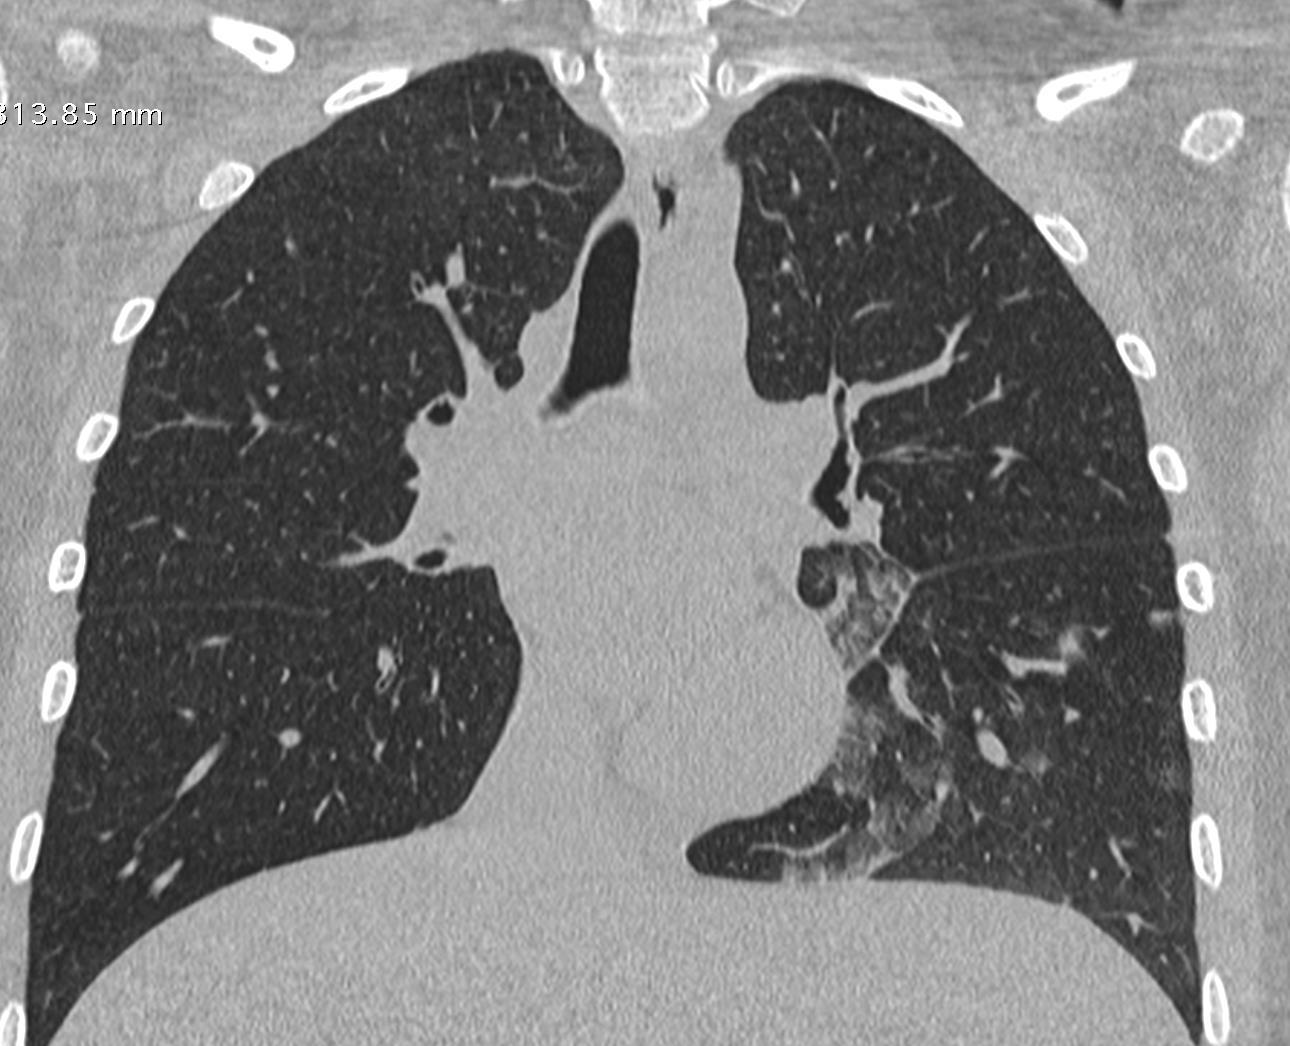

Acute Pediatric COVID-19: CT

21 Imaging of Covid 19 infection in children

3 Phases

Early: "Halo" sign

Local infection

Progressive: Diffuse GGO

Developed: Consolidation

Surr vasc congestion

Inflammation - adj alveoli

Alveoli fill with fluid/cells

• Bilateral & multifocal GGO, +/Consolidations or both

• Halo sign

• Peripheral and subpleural

• Bronchovascular thickening